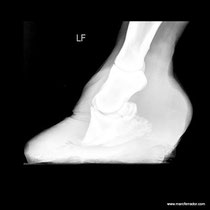

El casco es una estructura viva, que va creciendo en función de su desgaste. La dureza se rige por el terreno habitual del caballo y el tiempo que tiene que correr. Un caso es flexible ante irregularidades del suelo, tiene un efecto amortiguador que protege a las articulaciones del caballo y antideslizante en terrenos naturales, además funciona como un órgano sensitivo que transmite información importante al caballo sobre la consistencia del terreno.

Estando tapada por el hierro el casco no podrá hacer su función normal. Con herraduras la pezuña se queda sin estimular unas zonas de la suela que le son de vital importancia para su buen funcionamiento. También hay que decir que los agujeros de los clavos, aunque sean pocos, son unas vías abiertas en unas partes del estuche córnico muy estratégicas, quedando falcejades para este orificios verticales. La tapa que queda entre el suelo y el agujero de salida del clavo, perderá su función estructural y se rompe fácilmente pasando la presión que la tapa debería absorber, en otros puntos focalizados que probablemente no aguantan este exceso.